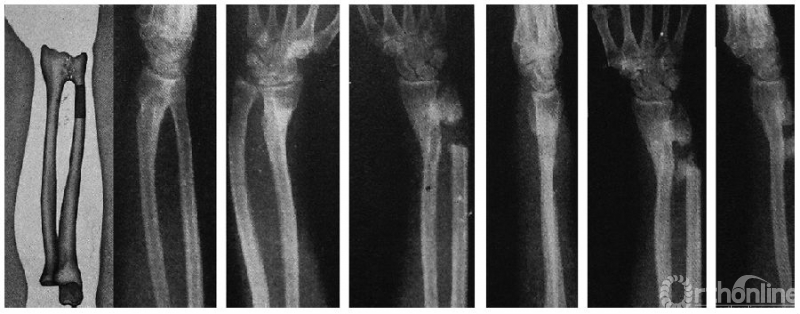

文献中Sauvé-Kapandji手术最早图片之一:最左侧为Steindler医生关于该术式的绘图描述,左至右分别是患者术前、术后和随访时的腕关节正侧位X线片

Sauvé医生和Kapandji医生最早提出的Sauvé-Kapandji手术由下尺桡关节融合术和尺骨远端假关节成形术构成,他们在去除尺骨远端骨干的同时也切除周围的骨膜和骨间膜,并用附近的肌肉或筋膜覆盖截骨端间隙以免术后骨化影响旋转活动,切除的骨段可被用做植骨材料。